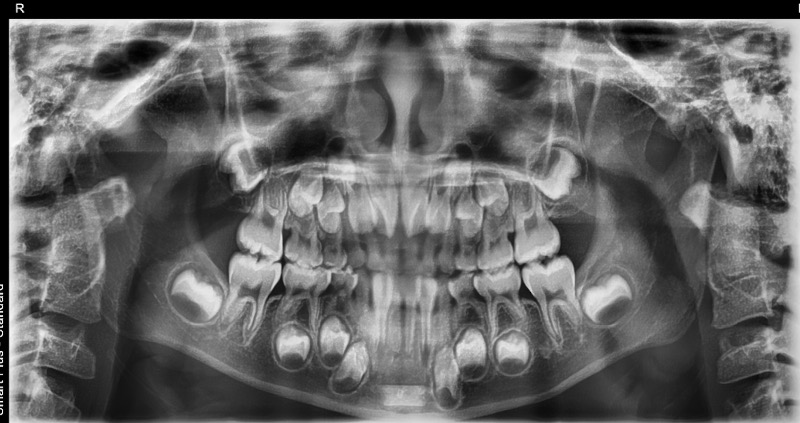

1、Hさん追加アライナーですが、歯列はだいたい並んでおります。年齢的に、下顎の成長時期にかかりますが何か指示することありますでしょうか。

パノラマが11月に入れてます。

下顎が左側変位し、下顎頭が右側に比べ小さいです。